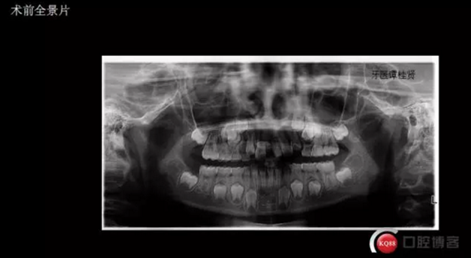

拔掉一顆后大概大半年時間很快就把間隙關閉了,但是由于還有一顆橫在兩中切牙間,牙縫始終得不到完全關閉,此時只能拔掉深部埋伏阻生的牙才能進一步矯正治療,但小孩一聽又要做一次手術有不同意了,這樣又拖了兩年多,長大了一些自然懂事了些。